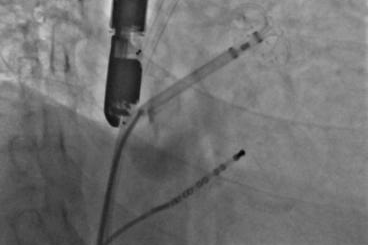

▲释放后,DSA与TEE观察均无残余分流

其中首场公开演示的左心耳血栓封堵病例具有极高难度,患者术前TEE显示左心耳血栓形成伴机化,血栓位于心耳中段,近中端絮状物明显。封堵机会只有一次,选型和操作稍有失误,都会增加手术风险。因此手术采取全麻,并安装了抗栓塞脑动脉保护装置,以减少术中风险。通过TEE引导下测量左心耳大小以及确认左心耳血栓位置,李岳春教授凭借自身丰富经验最终决定使用LAmbre 2632型号,采用推送式植入法将左心耳血栓牢牢锁死于远端,并且封堵器一次成型,封堵效果极佳,结束后取出脑保护装置,均未见血栓,顺利完成了此台高难度的手术,获得了学员们的一致认可。